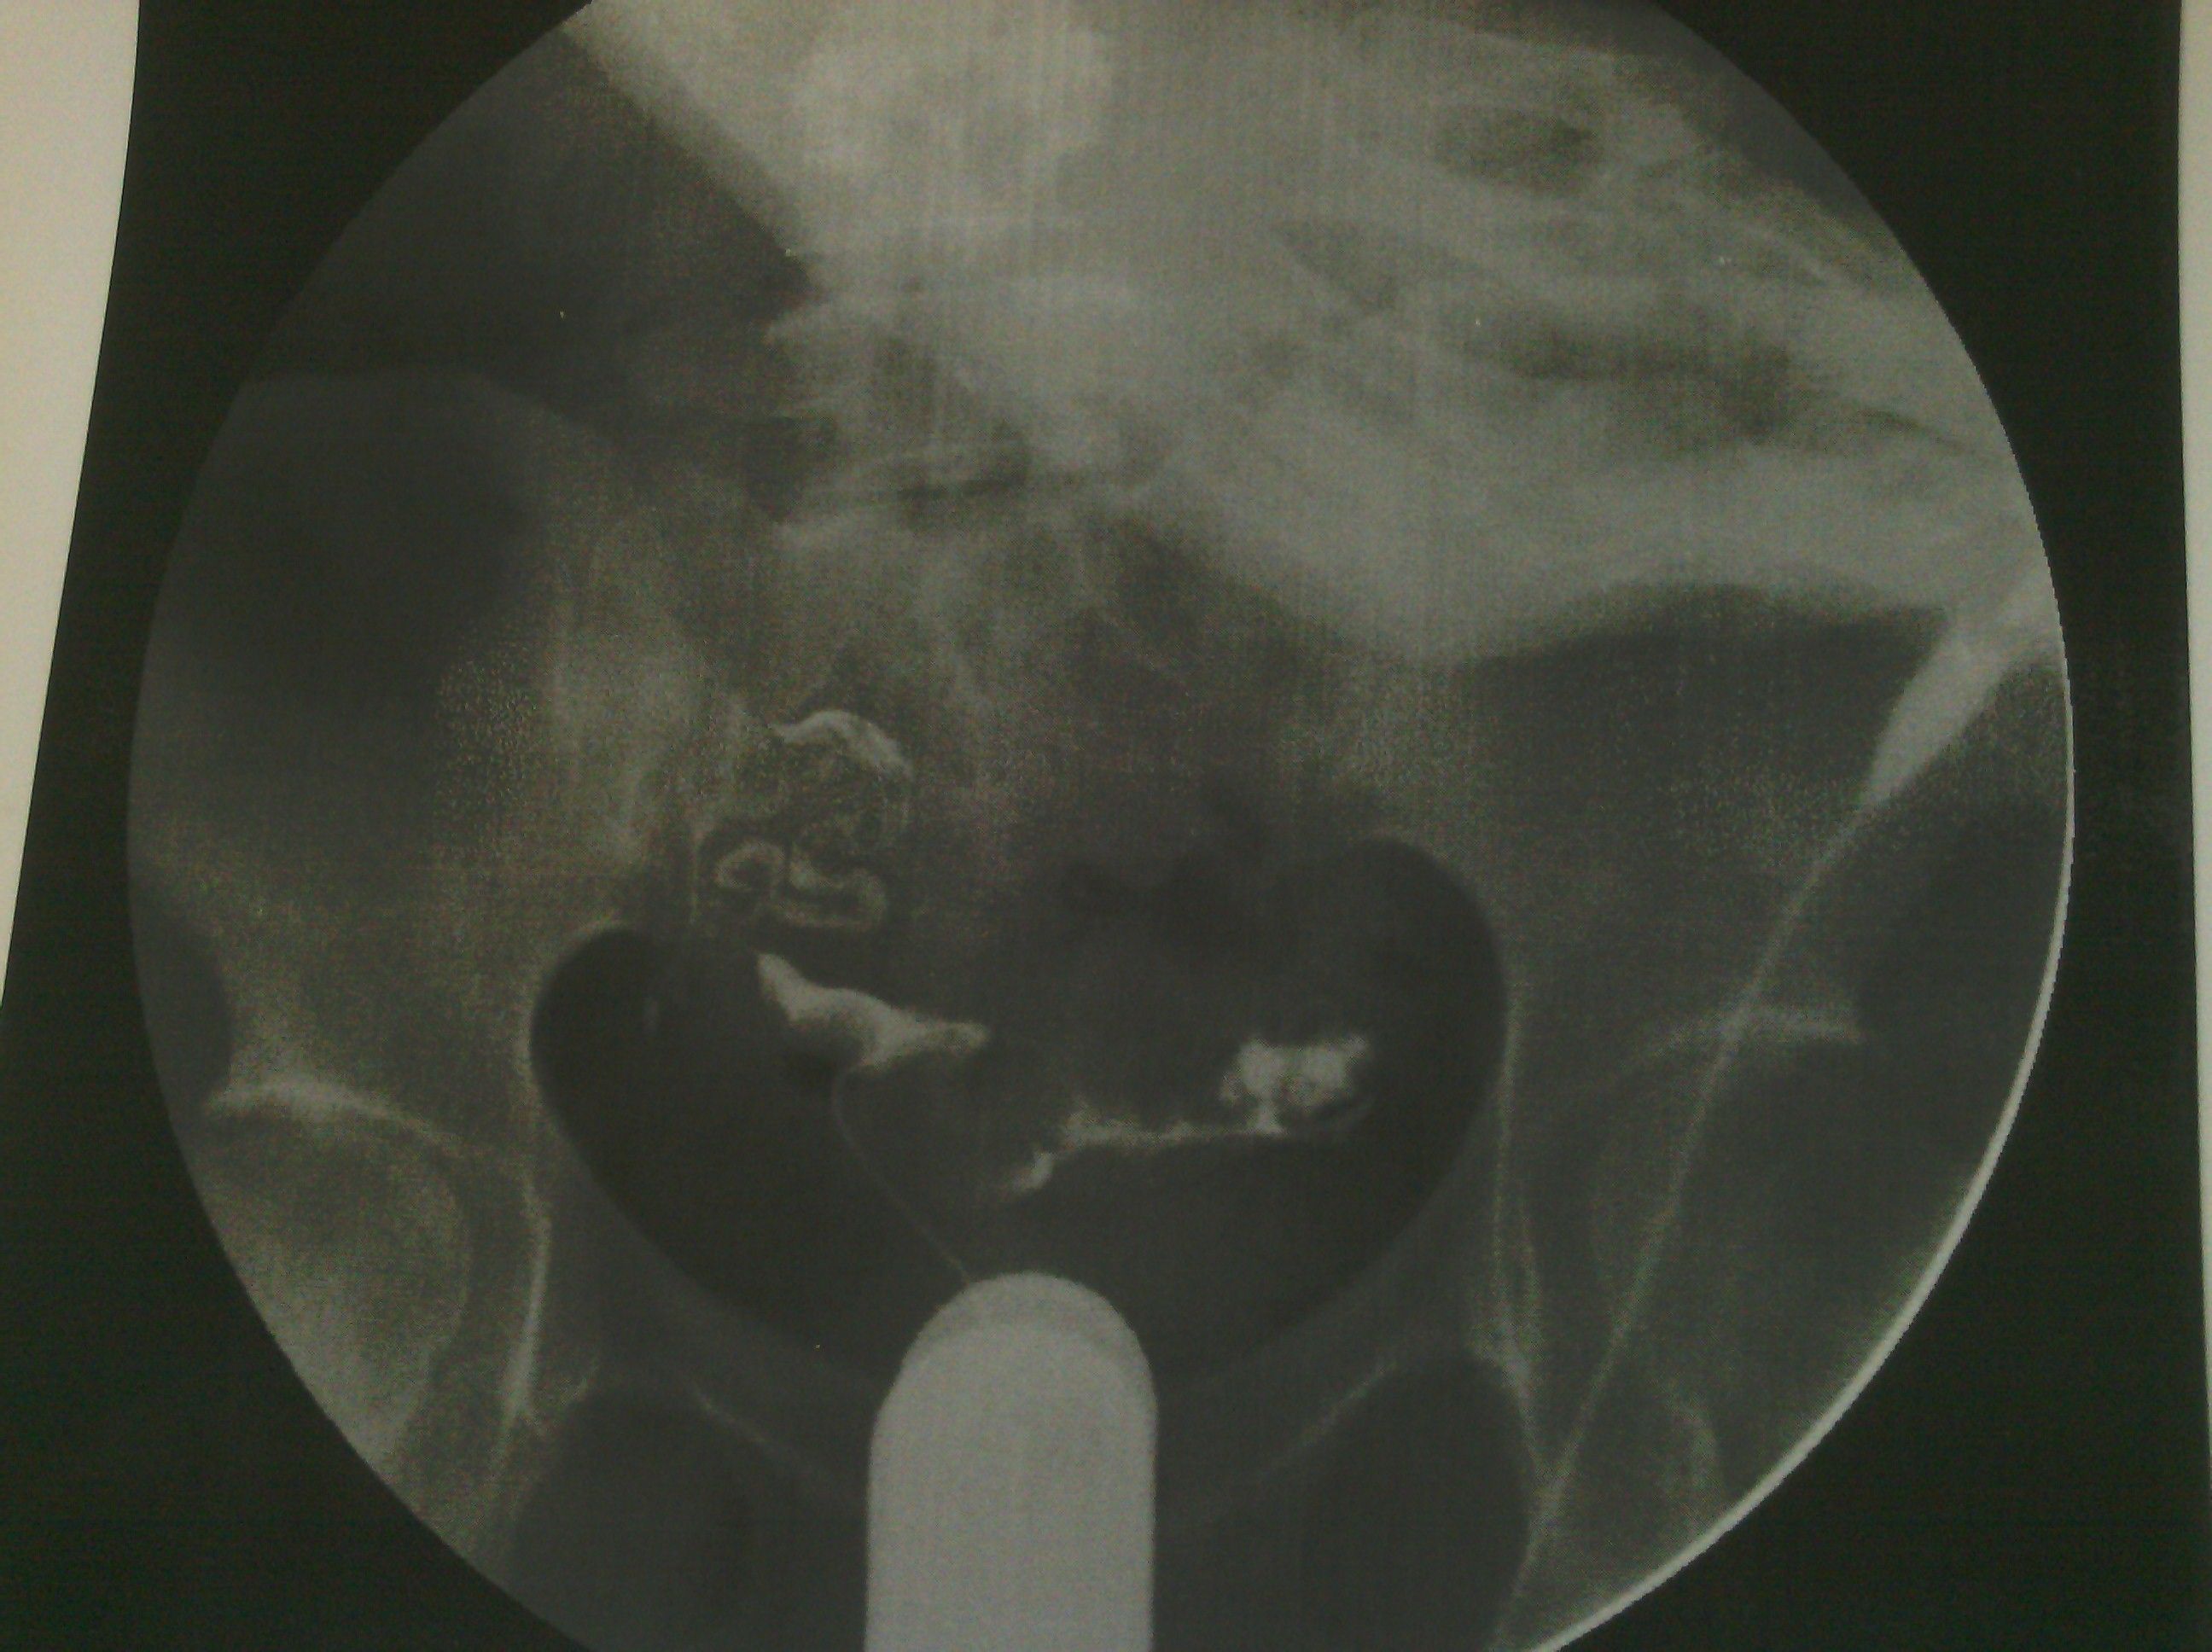

最新输卵管造影图片,麻烦各位大侠帮忙看看,纠结中 各位好,这是我11月6日做的输卵管造影图片,麻烦给看看现在是什么情况。在医院光说通而不畅有粘连,也没说哪个部位粘连,具体的是哪个部位有毛病呢?是间质部,峡部或是壶部。说少量弥散,然而弥散的片子也没延迟拍摄,是造影后直接就出来了,那判断的标准准确吗?看了好几年的病了,慕名到哪个医院去了,都没给过我合理化的建议,都是到哪家,哪家哪个拿手就推荐你做哪个,我现在看见医院两个字就想吐。我就是想,死,我也得死个明白。麻烦各位好心人看看我的片子给我一个合理化建议。现在的输卵管造影是个什么情况应该怎样治疗,在此拜谢各位了。我没啥财富值,对不起各位了。望能看片子解释一二,不胜感激。 点击展开 母婴用户710320885 2013-11-09 08:05 为您推荐: 其他回答 片子没标左右 所以我不清楚是哪边。 可以告诉你的是 面对我左边的输卵管走形上举,有黏连。面对右边的输卵管扭曲扩张。整个状况不是很乐观,具体治疗请咨询妇产科医生。 匿名用户 2013-11-11 14:28 相关问题 求讲解输卵管造影图片 妇科医生专家好:请帮忙看看这份“子宫输卵管造影检查报告”: 帮忙看看造影的报告,双侧输卵管炎不能怀孕了吗?

各位好,这是我11月6日做的输卵管造影图片,麻烦给看看现在是什么情况。在医院光说通而不畅有粘连,也没说哪个部位粘连,具体的是哪个部位有毛病呢?是间质部,峡部或是壶部。说少量弥散,然而弥散的片子也没延迟拍摄,是造影后直接就出来了,那判断的标准准确吗?看了好几年的病了,慕名到哪个医院去了,都没给过我合理化的建议,都是到哪家,哪家哪个拿手就推荐你做哪个,我现在看见医院两个字就想吐。我就是想,死,我也得死个明白。麻烦各位好心人看看我的片子给我一个合理化建议。现在的输卵管造影是个什么情况应该怎样治疗,在此拜谢各位了。我没啥财富值,对不起各位了。望能看片子解释一二,不胜感激。